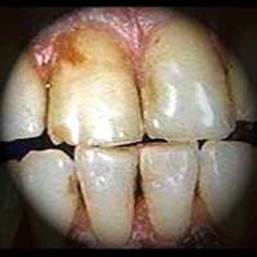

При хроническом отравлении никотином развиваютВнся болезненные состояния различных участков желудочВнно-кишечного тракта. Вследствие раздражения никотином нервных окончаний слюнных желез повышается слюноотделение, что вынуждает курящего сплевывать или глотать слюну, в которой находится ряд веществ табачного дыма. Раздражается слизистая оболочка полости рта. Никотин, откладываясь на слизистой оболочке десен и зубах, постоянно раздражает нервные окончания. Десны становятся рыхлыми, кровоточат, повреждается зубная эмаль. Зубы выглядят почерневшими, рано порВнтятся (Влкариес курильщиковВ»). При курении нередко расшатываются зубы, что ведет к их выпадению и восВнпалению десен. Особенно вредно действует на пищеваВнрение привычка заглатывать табачный дым, курить наВнтощак, а также непосредственно после еды и в ночное время. В результате снижается аппетит, так как никоВнтин тормозит сократительную деятельность желудка, от которой зависит в значительной мере ощущение голода. Могут отмечаться такие болезненные явления, как тошВннота, рвота, боли в желудке и кишечнике.